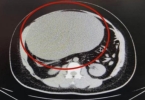

• 女子肚子变大以为发胖,腹痛送医从肚中取出16斤囊肿

女子肚子变大以为发胖,腹痛送医从肚中取出16斤囊肿

近日河南郑州一位21岁的女生晓琪,在早上厕所后腹痛难忍,痛到几乎不能走路。拨打120送往医院后,医生发现晓琪的腹部很大堪比怀孕,而她自己却以为是长胖自行服用了3个月的减肥药。如果不是这次腹痛难忍,她可能还不 ...